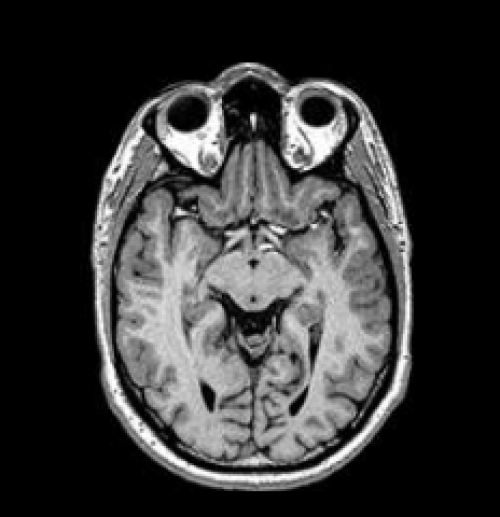

Аксиальная плоскость